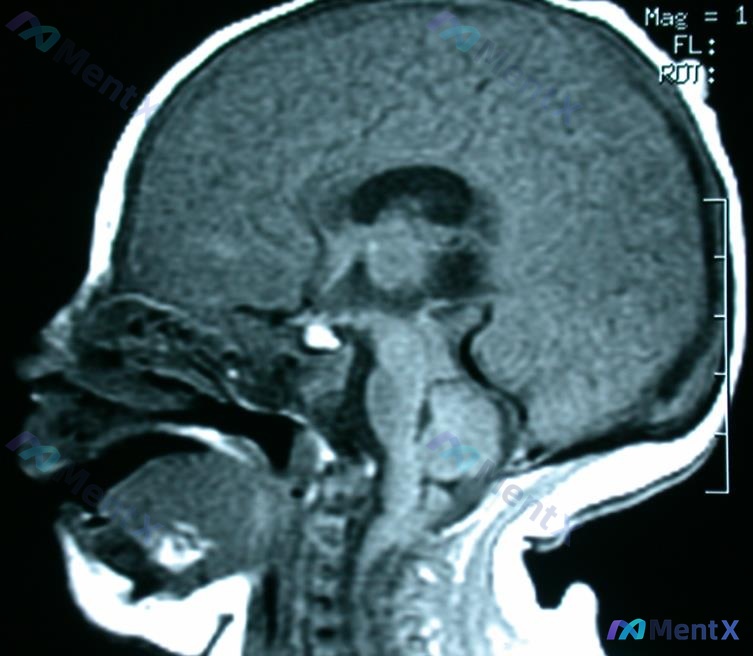

今天看到一份脑部MRI资料,觉得这个读片思路挺有警示意义的,整理一下和大家分享。 影像核心信息 - 序列:脑部MRI 矢状位 增强前梯度回波3D T1加权像 - 主要阳性发现:额顶叶区域(紧贴颅骨内板下方)可见一条带状高信号影,信号强度接近皮下脂肪/骨髓信号 - 关键阴性表现:中线结构居中,脑沟未见...

整理到一个有点意思的早产新生儿病例,可能涉及临床思维陷阱,放出来大家讨论: 基本情况:33周早产男性新生儿,G1P0,母亲产前护理不一致、未服用产前维生素,既往史有反馈控制不良(推测是癫痫?)。 目前看到的表现:有自发的手臂运动,但存在下肢弛缓性瘫痪(原文里提的核心表现)。身高、体重、头围分别在第2...